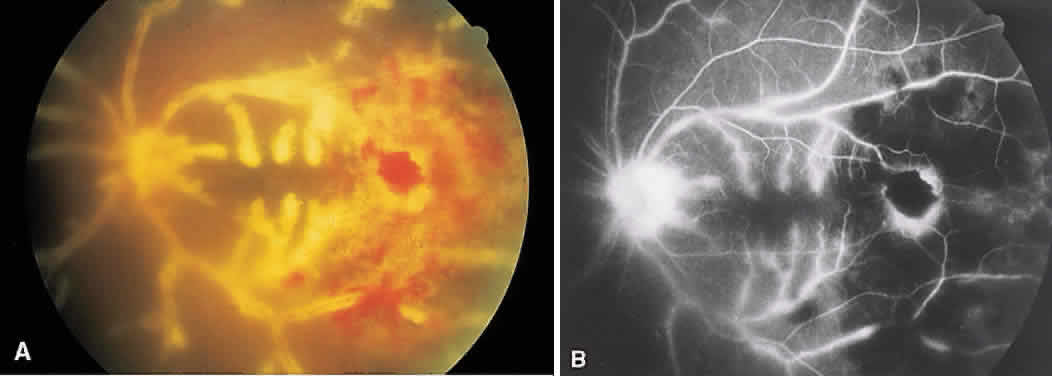

Tuberculosis has numerous ocular presentations, including anterior uveitis, scleritis, sclerokeratitis, phlyctenulosis, interstitial keratitis, choroidal granulomas (often with serous elevations; Fig. 23A),retinal exudate, macular star formation, retinal vas-culitis, vitreous cells, SRNV, and optic nerve granulomas. Eales' disease, a bilateral peripheral vasculitis with peripheral neovascularization and vitreous hemorrhage, frequently occurs in young men who have positive purified protein derivative test results (Fig. 24).

Fig. 23. Tuberculoma. A. Subretinal tuberculoma. B. Multiple loculated areas of hyperfluorescence due to pooling of dye beneath the sensory retina.

Fig. 24. Eales' disease (retinal vasculitis). A. Angiography of the left disc shows staining of the retinal vessels, particularly the venules in the late venous stage. B. In the far periphery, there is staining of the peripheral vessels (particularly venules) just adjacent to an area of nonperfused retina. The hypofluorescent areas represent intraretinal hemorrhages.

On fluorescein angiography, a choroidal tuberculoma hyperfluoresces in the late phase (see Fig. 23B). There may be leakage and pooling of dye if there is a serous retinal detachment. As the tuberculoma responds to therapy, the hyperfluorescence decreases and pockets of hypofluorescence can be seen.79 Retinal arteriovenous shunts with dilated capillaries also can be seen in the granuloma.80 Peri-phlebitis causes capillary dropout and venous staining. Neovascularization of the peripheral retina is not uncommon.